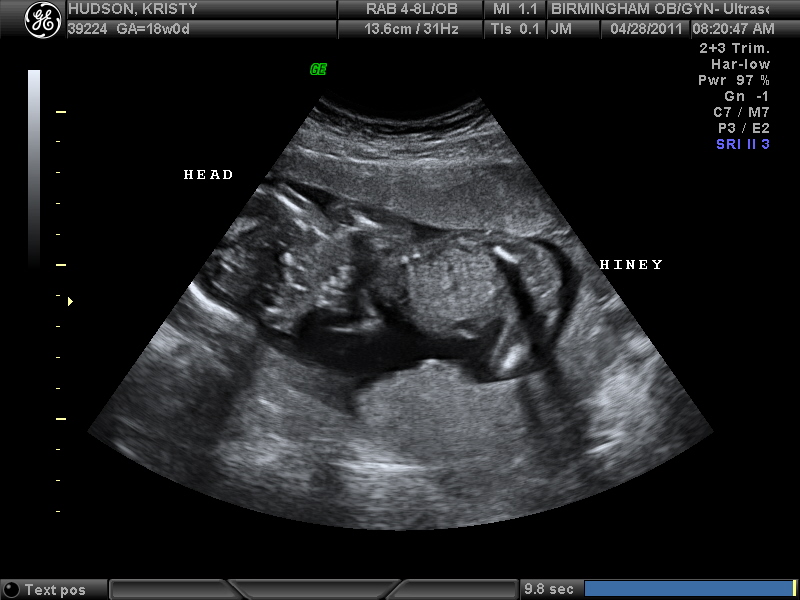

Gender: It's a GIRL! Peyton Lea! We found out today!

We had our 18 week appointment this morning. Little girl is a wiggle worm! When we first went in she was laying in a position where we couldn't tell what she was. That didn't last long. As the lady started the exam Peyton started the show! She rolled for us a couple of times. Her legs NEVER stopped moving. It is something I will never forget! She was standing in there at one point.

She is 9oz and measuring 6 days early.

Finally here is Ms Peyton Lea Hudson